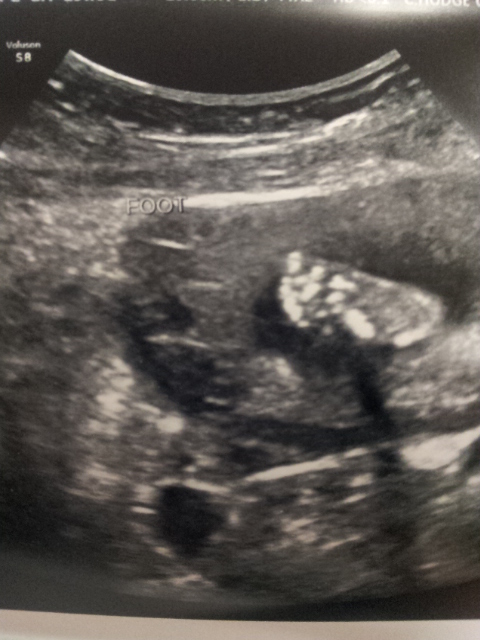

Had my anatomy scan this morning. We waited for over 40 minutes in the waiting room, and thre boys were so good. Finally got to the ultrasound room and everything looked great! All measurements match perfectly to my due date, and baby's heart rate was 147.

Re: AW: Awesome A/S and we're having a... *** Updated with pics***